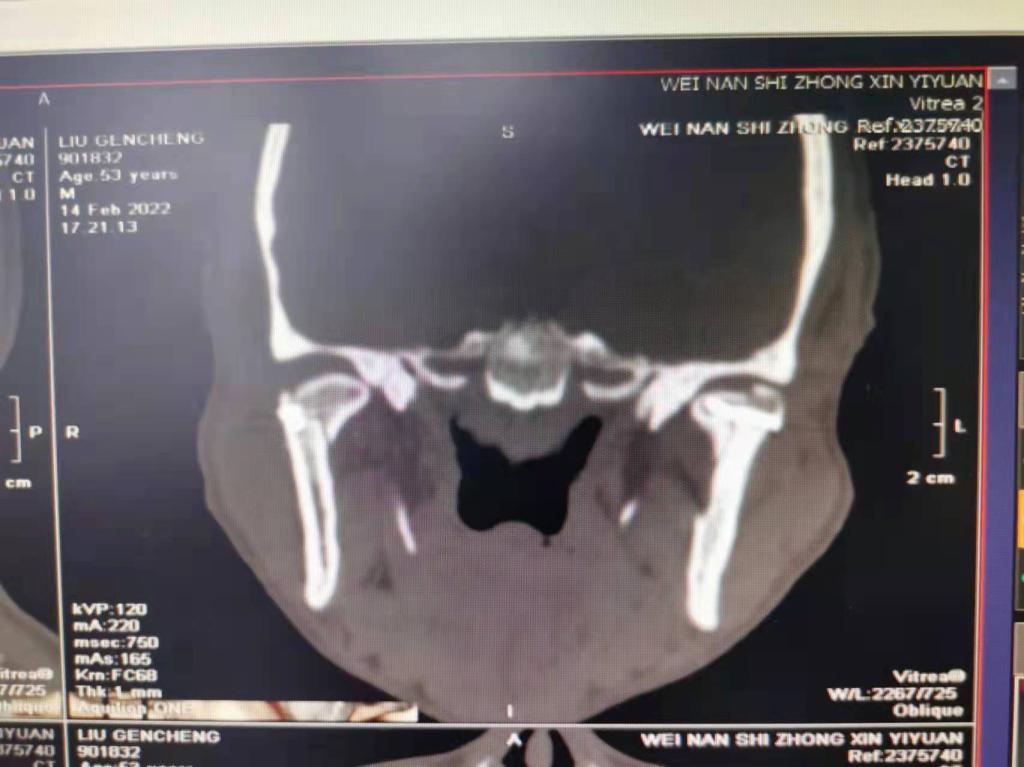

据了解,53岁的患者刘先生在1月25日当天走路不慎摔倒致下颌损伤,造成颏部软组织裂伤和张口困难,前往当地卫生院进行颏部裂伤清创缝合术。术后辗转到MILAN.COM口腔科门诊就诊,并进行颌面部CT检查提示为下颌颏部正中和双侧髁状突骨折,双侧下颌升支高度不一致,右侧较左侧变短1cm,张口重度困难,咬合关系错乱。刘先生因考虑在春节过后再入院治疗,于2月8日再次前来口腔科以“下颌骨骨折”收治人院。

口腔科主治医师蔺非非为患者入院后进行完善术前常规检查和颌间牵引恢复咬合关系。科主任李瑞春结合患者实际病情和检查结果认为,患者的髁突骨折在下颌骨骨折中所占比例较高,约为17.0%-36.3%。髁突骨折时,耳前区有明显的疼痛,局部肿胀、压痛。通过手指深入外耳道或在髁突部触诊,如张口时髁突运动消失,可能有骨折段移位。双侧低位骨折时,2个髁突均被翼外肌拉向前内方,双侧下颌支被拉向上方,可出现后牙早接触,前牙开秴。髁状突骨折易引起下颌后缩,张口困难,咬合关系错乱,关节强直等并发症。考虑患者系陈旧性骨折应尽早实施手术,避免骨折导致的张口困难、关节强直等并发症。因患者已经错过最佳治疗时期,决定尽快为患者进行手术治疗。

科主任李瑞春和主治医师蔺非非经过缜密的术前讨论和充分评估,手术在全身麻醉下进行,术中克服术野狭小操作不便困难,将下颌骨骨折完好对位,顺利地完成了"双侧髁状突和下颌颏部正中骨折切开复位内固定术"。术后检查患者面部对称,双侧下颌升支高度一致,咬合关系已恢复。